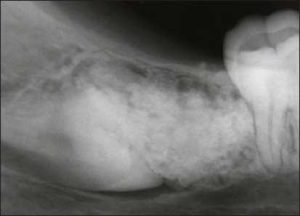

All retained roots or root fractures that are close to the tissue surface or exhibit pathological signs should be removed (Figure 10-2).